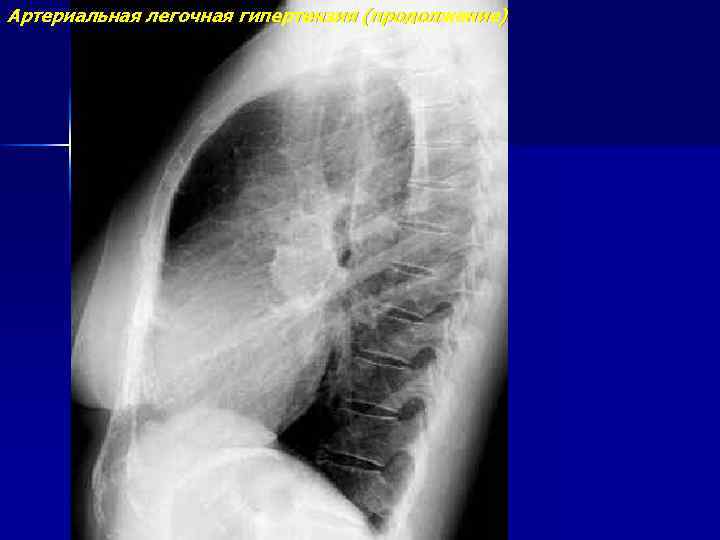

Артериальная легочная гипертензия (продолжение)